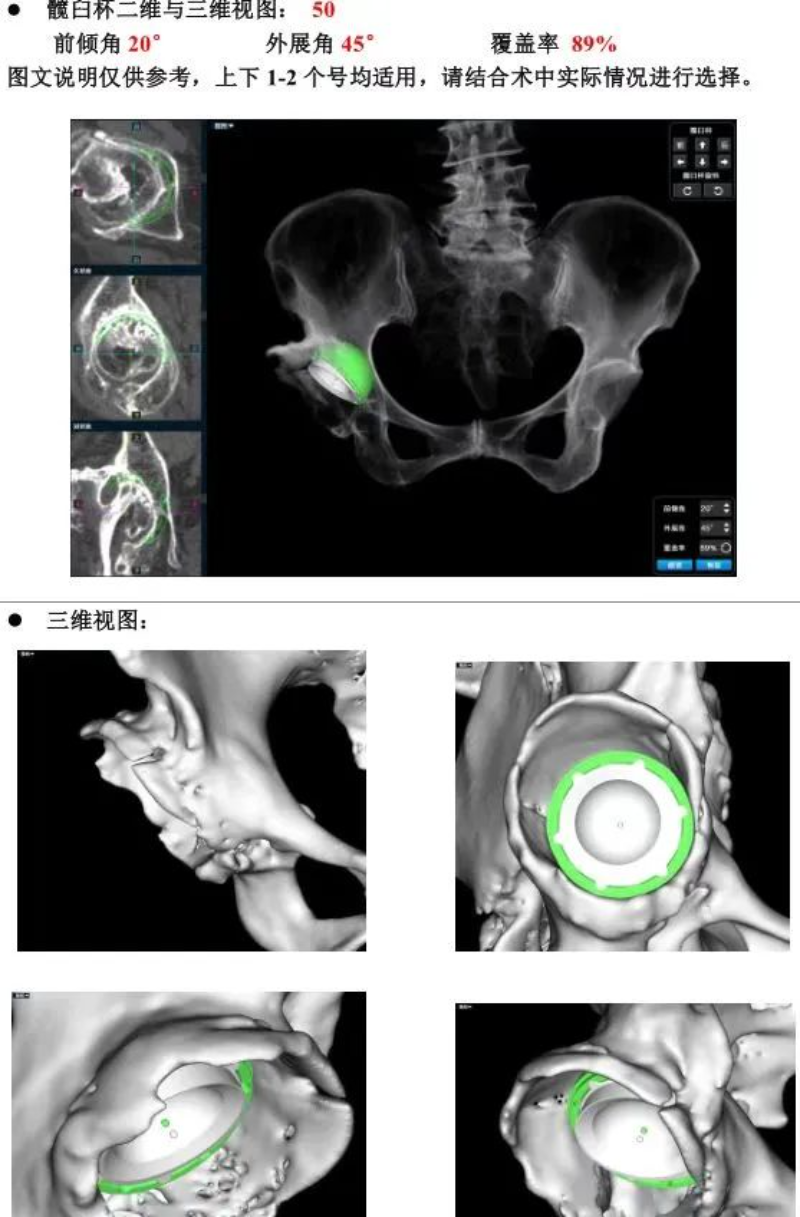

△AI術(shù)前策劃

文章配圖

50多歲的朱大哥,20多年前因為車禍傷導(dǎo)致股骨頭缺血性壞死,一直一瘸一拐走路,就診時,右側(cè)髖關(guān)節(jié)股骨頭基本消失,髖臼磨損嚴(yán)重,關(guān)節(jié)已接近融合,肢體短縮有6-7cm,通過術(shù)前AI規(guī)劃,能精準(zhǔn)確定截骨的位置,髖臼杯安放的角度和尺寸等。手術(shù)進(jìn)展順利,術(shù)后關(guān)節(jié)功能恢復(fù)良好,肢體短縮明顯糾正無神經(jīng)損傷等并發(fā)癥,一個月后復(fù)查關(guān)節(jié)穩(wěn)定,患者從此告別一瘸一拐的日子。